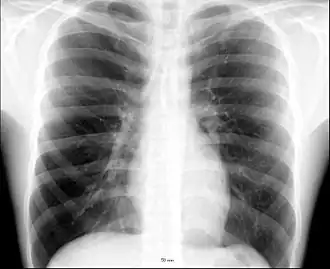

The human thorax includes the thoracic cavity and the thoracic wall. It contains organs including the heart, lungs, and thymus gland, as well as muscles and various other internal structures. The chest may be affected by many diseases, of which the most common symptom is chest pain.

The contents of the thorax include the heart and lungs (and the thymus gland); the major and minor pectoral muscles, trapezius muscles, and neck muscle; and internal structures such as the diaphragm, the esophagus, the trachea, and a part of the sternum known as the xiphoid process. Arteries and veins are also contained – (aorta, superior vena cava, inferior vena cava and the pulmonary artery); bones (the shoulder socket containing the upper part of the humerus, the scapula, sternum, thoracic portion of the spine, collarbone, and the rib cage and floating ribs).

Different types of diseases or conditions that affect the chest include pleurisy, flail chest, atelectasis, and the most common condition, chest pain. These conditions can be hereditary or caused by birth defects or trauma. Any condition that lowers the ability to either breathe deeply or to cough is considered a chest disease or condition.